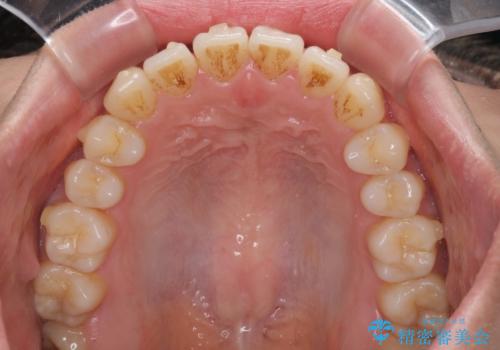

オープンバイトでかみにくい インビザラインによる矯正治療

- 前歯の上下スペースによる食べにくさを気にして来院された患者様です。

インビザラインにより上下の前歯の隙間を閉じていくこととしました。

上下の奥歯を圧下させるようにすることで、前歯を接触させるように計画しました。

上下の隙間に舌が入り込むことがオープンバイトの原因であったため、舌の筋肉のトレーニングも並行して行い、後戻りの抑制を図りました。